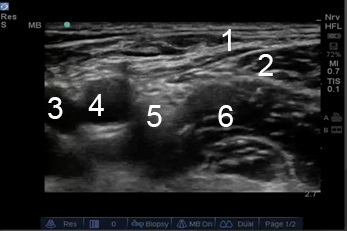

Femoral Nerve Anatomy Image

1. Fascia Lata

2. Fascia Iliaca

3. Femoral Vein

4. Femoral Artery

5. Femoral Nerve

6. Iliacus Muscle